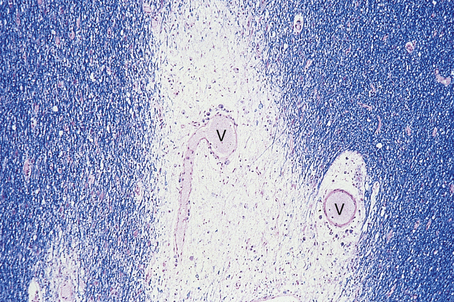

Infection of the brain is a well-recognised complication of several common viral illnesses. Most cases are mild, self-limiting conditions, but others, such as rabies and herpes simplex type I infections, result in extensive tissue destruction and are often fatal. Herpes simplex encephalitis is the commonest variety of acute viral encephalitis in the UK. Despite these differences in severity, all viral infections of the brain and spinal cord produce similar pathological changes in the CNS:

mononuclear cell infiltration by lymphocytes, plasma cells and macrophages; this is often noticeable as perivascular cuffing which usually extends into the parenchyma (Fig. 26.15)

cell lysis (cytolytic viral infection) and phagocytosis of cell debris by macrophages; when neurones are involved, for example as in poliovirus infection, this process is known as neuronophagia

viral inclusions, which can often be detected in infected neurones or glial cells; occasionally, these can be of diagnostic value, for example ‘owl-eye’ inclusions in cytomegalovirus infection, or Negri bodies in rabies

reactive hypertrophy and hyperplasia of astrocytes and microglial cells, often forming cell clusters

oedema, which is of vasogenic type.

image

Fig. 26.15 Acute viral encephalitis due to herpes simplex virus. A blood vessel (V) in the grey matter is surrounded by a dense aggregate of lymphocytes and plasma cells, which have crossed the blood–brain barrier and migrated into the surrounding temporal lobe.